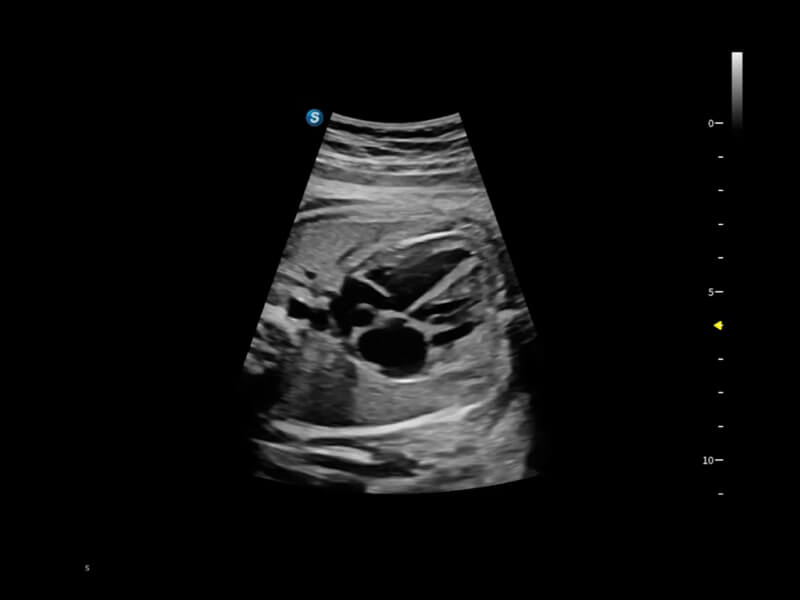

作为开立医疗全新打造的超高端旗舰超声产品,从探头抬起唤醒开启扫查到多维探头发射接收,通过先进的场成像发射、自适应聚合重建等技术,基于RF Data原始射频数据在图像生成、高端功能等方面实现突破,为妇产科、儿科提供全方位临床解决方案。

梦溪®P80以“关爱女性”为基石,提供全方位的解决方案,量身定制以满足女性的健康需求,涵盖妇科、生殖健康检查、产前筛查及产后康复等领域。